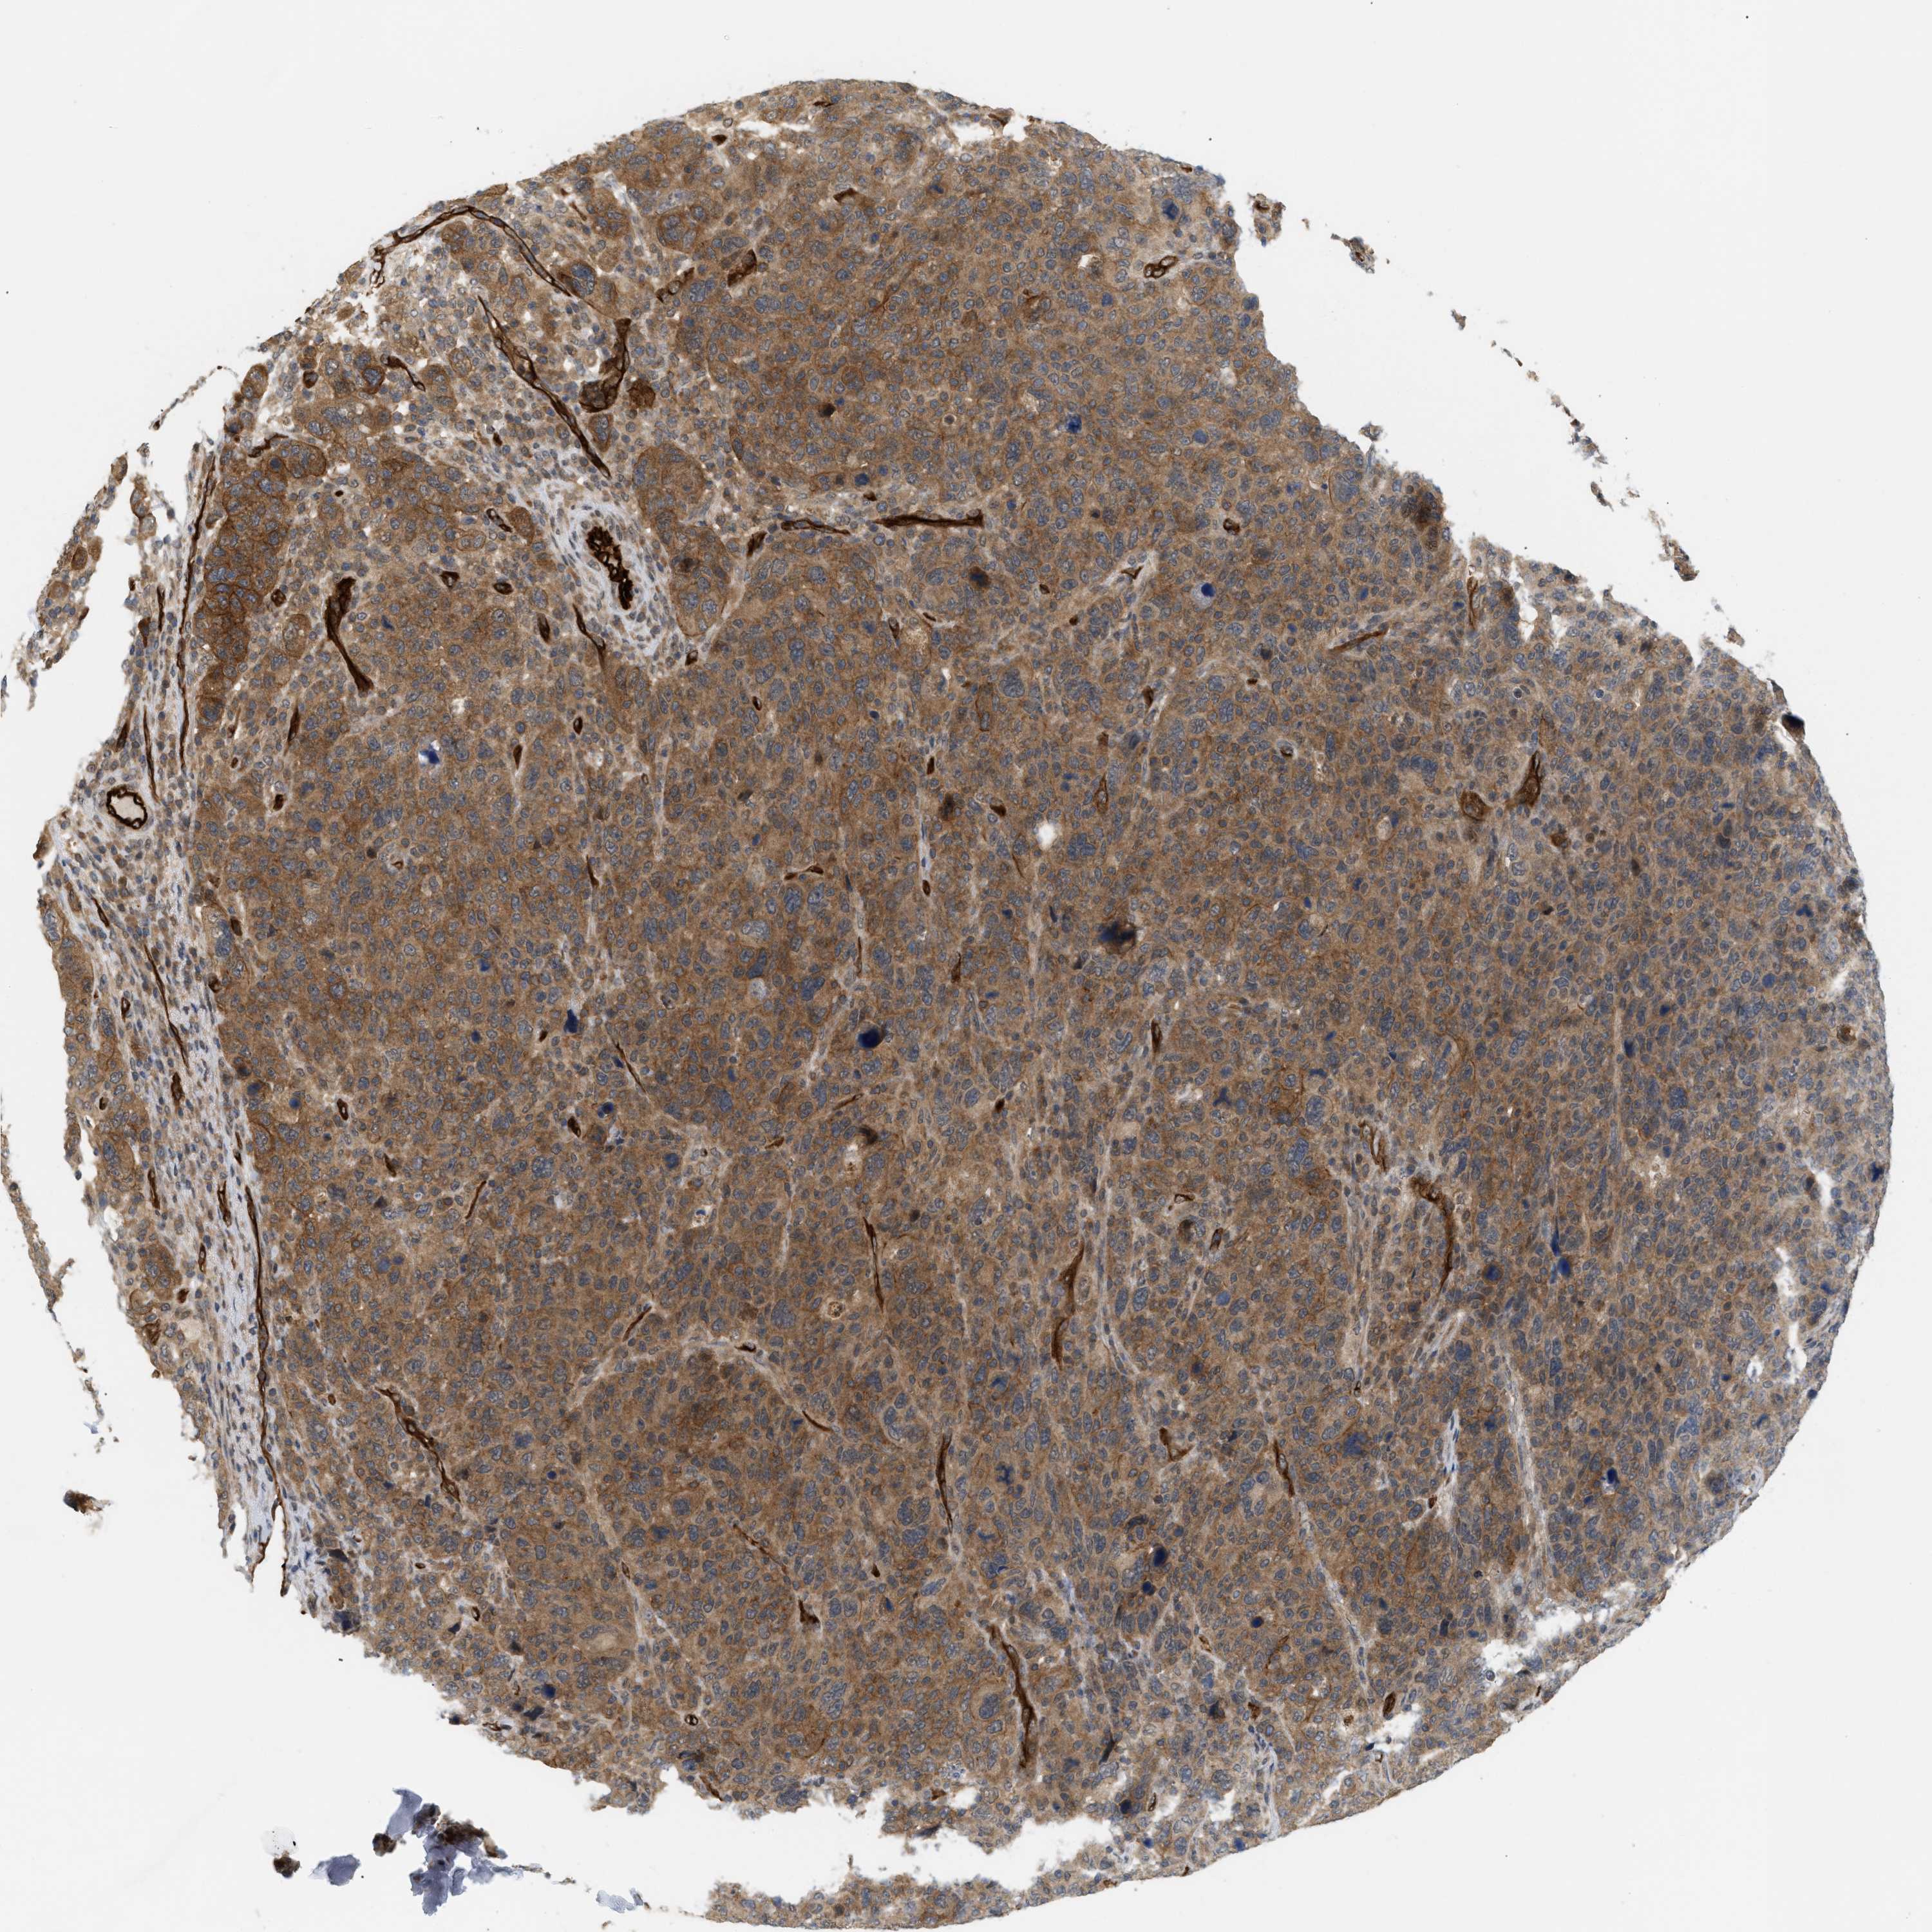

BRCA TCGA BRCA VALIDATION PROTEIN EXPRESSION